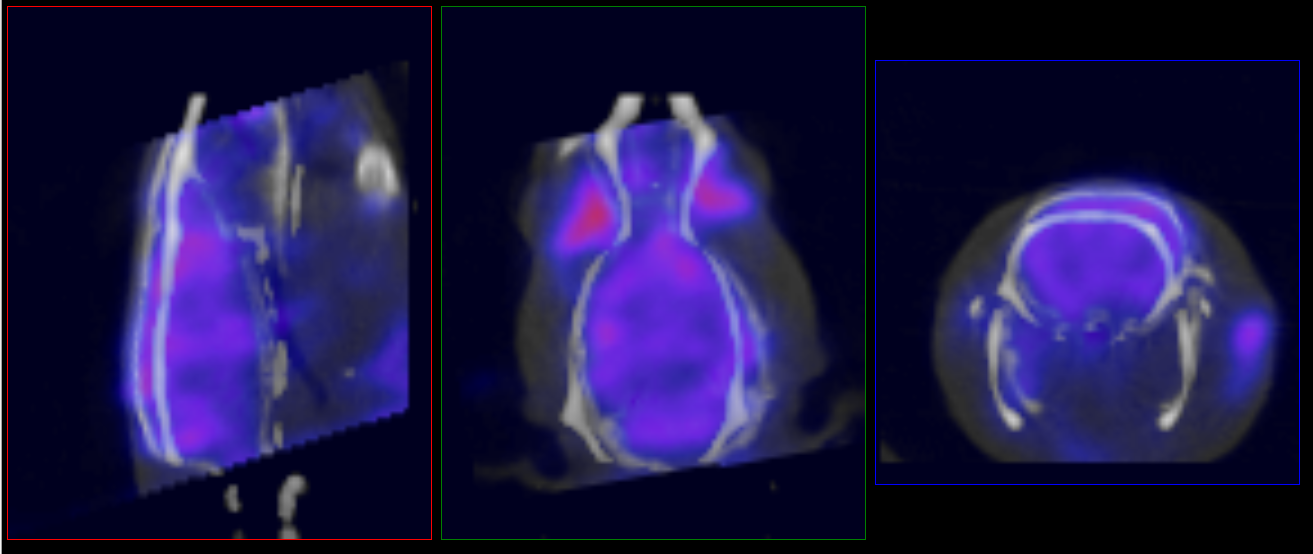

Manual Correction

Sometimes automatic registration will be poor and will need manual correction.

To manually edit the registration, load the ‘atlasFinal-anatomical.mhd’ file from the output directory and place it in the reference position. Navigate to the Reorientation/Registration operator and manually correct the registration:

- Data to Atlas (seen in example image below): Register all inputs to the atlas anatomical reference.

- Atlas to Data: Register the atlas anatomical reference to the input anatomical. Apply this transform to the ROI.

Once satisfied with the registration, unload the atlas anatomical reference and rerun the tool using the “Import 3D ROI” option under the advanced settings tab.